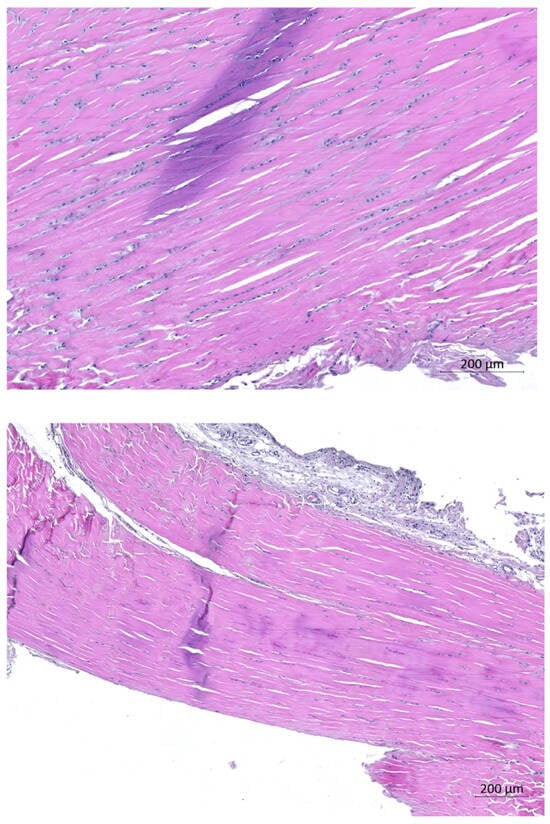

Histomorphometric Evaluation